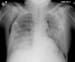

This patient was undergoing treatment for acute respiratory distress syndrome when a new lucency was found on a routine portable chest radiograph. The lucency over the right midlung zone represents a subpleural air cyst. Such cysts can increase in size and eventually rupture, creating a pneumothorax.